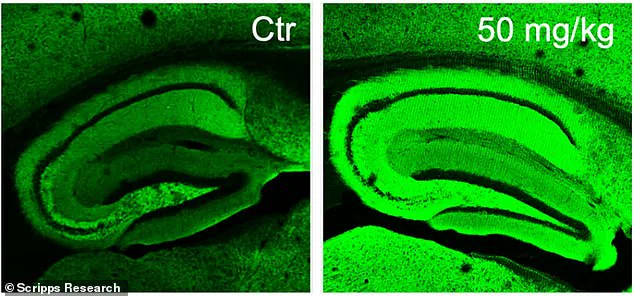

Three different doses—10, 20, and 50 milligrams—were tested in varying combinations to determine the optimal dosage. After the treatment period, cognitive assessments were conducted on the mice using both a water maze test and a fear-conditioning experiment designed to evaluate their memory retention capabilities. Healthy mice typically perform better at finding the hidden platform in the water maze over time, whereas Alzheimer’s-affected mice struggle with this task.

The results were promising for those receiving diAcCA treatment. Mice treated with higher doses of the compound swam faster and spent more time near the previously located platform, indicating improved memory retention compared to untreated control groups. Similarly, in the fear test, treated mice exhibited a greater tendency to freeze upon hearing the conditioned stimulus, demonstrating enhanced recall of the associated fear.

Beyond cognitive performance improvements, brain tissue analysis revealed fewer plaques and tangles characteristic of Alzheimer’s disease, along with increased synaptic connections and reduced inflammation in treated animals. ‘By combating inflammation and oxidative stress with this diAcCA compound, we actually increased the number of synapses in the brain,’ Dr. Lipton explained.